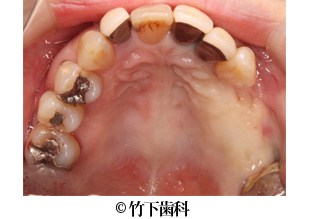

【症例2】右下臼歯部3本欠損のインプラントによる治療

- 治療前

- 治療後

- 治療名

- 右下臼歯部3本欠損のインプラントによる治療

- 費用

- 605,000円(税込)

【内訳】

インプラント埋入術

220,000円(税込) × 2

インプラント上部構造

55,000円(税込) × 3

- 期間

- 5ヵ月

- 通院回数

- 11回

- 患者様

- 50代女性

治療内容

患者様の症状

部分入れ歯を長年使用していて、奥歯で噛むことに困難を感じていました。食べ応えのあるものをしっかりと噛みたいというご希望がありました。

治療法

下顎の欠損部分に2本の人工の歯根を埋入しました。そこに3本の歯の形をしたブリッジの上部構造を装着しました。

治療結果

インプラント埋入術によって人工歯根を形成し、その上に上部構造を作ったことで、ご本人の歯のように安定して食べものを噛めるようになりました。2本のインプラントにブリッジの上部構造を装着することで、3本の歯があるような見た目になりました。

そのほか

患者様のご希望を聞いて、天然歯はなるべく残すような治療をしています。

※治療結果は患者様によって個人差があります。

治療を行う上での 注意点 (リスク・副作用)

出血、腫脹、疼痛、神経麻痺、補綴物のダツリ、破折、インプラント体の破折、咬合違和感、インプラント周囲炎